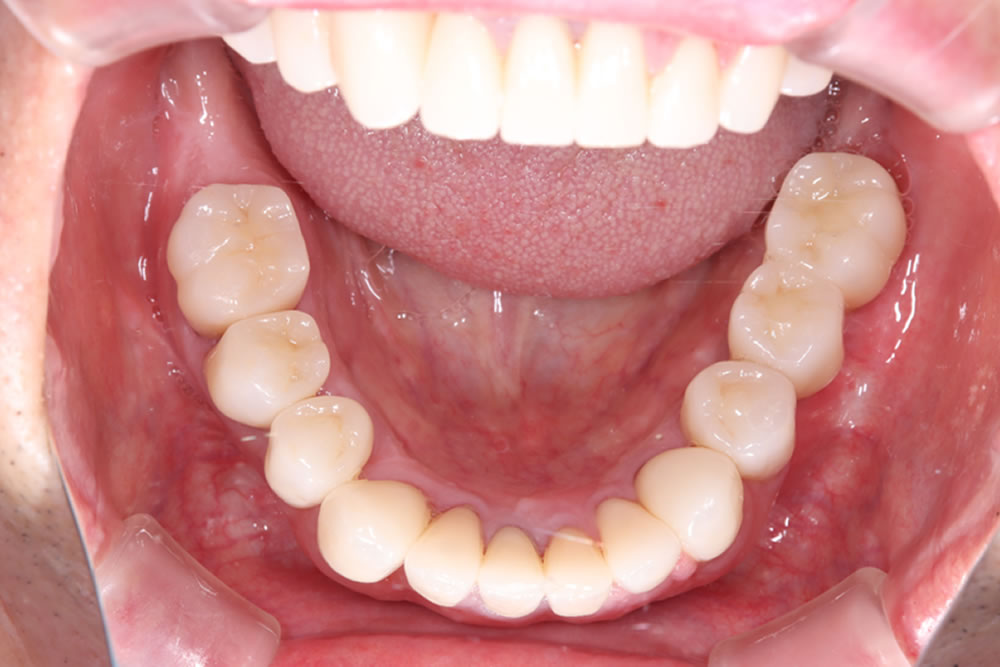

治療終了時の口腔内

下顎はインプラントおよびセラミックによる補綴治療を行い、上顎は保険適用の義歯を装着しています。